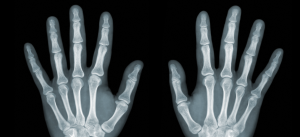

Erosive Arthritis

Erosive Arthritis: How This Autoimmune Disease Starts in Your Gut Erosive arthritis is one of the most aggressive and destructive forms of arthritis that can affect your joints, especially in your hands and feet. It causes severe inflammation, pain, and erosion of the bone and cartilage, leading to deformities and